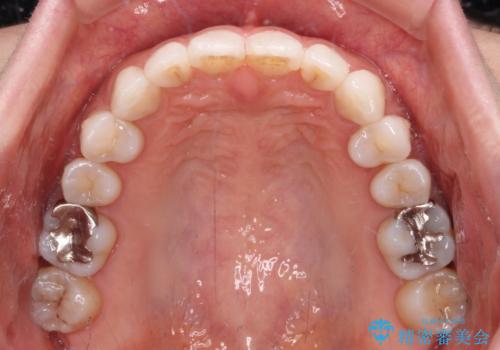

- 前歯のデコボコを気にして来院された患者様です。

歯列不正が軽度であり、インビザラインの装着時間を遵守してくださったため、日本と海外を行き来しながらも2年弱でしっかりと仕上げることができました。